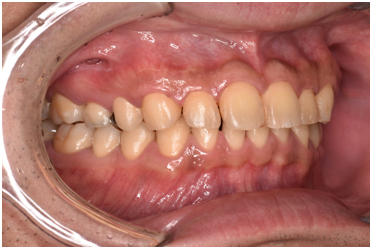

治療前

| カウンセリング・診断結果 | 診察したところ、全体的に歯石が付着していて、特に歯茎の下には黒い歯石が付着していました。 歯茎も赤く腫れており、歯周病の検査を行ったところ、全体的に歯周病が進行し、中等度の歯周炎が認められました。 |